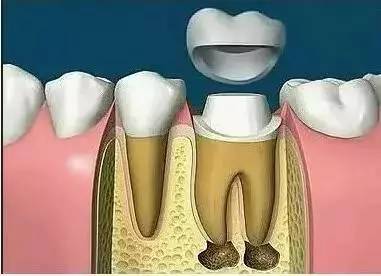

根管治疗后为何还需要做全冠保护?

很多人不理解,在根管治疗后,牙齿不疼了,补上就可以了,为什么还要做全冠保护,觉得没有必要。

事实上在根管治疗后,没有牙髓提供营养的牙齿会变脆,剩余的牙冠部分很容易折断劈裂,导致牙齿使用寿命减少,因此根管治疗后需做全冠对其进行保护。